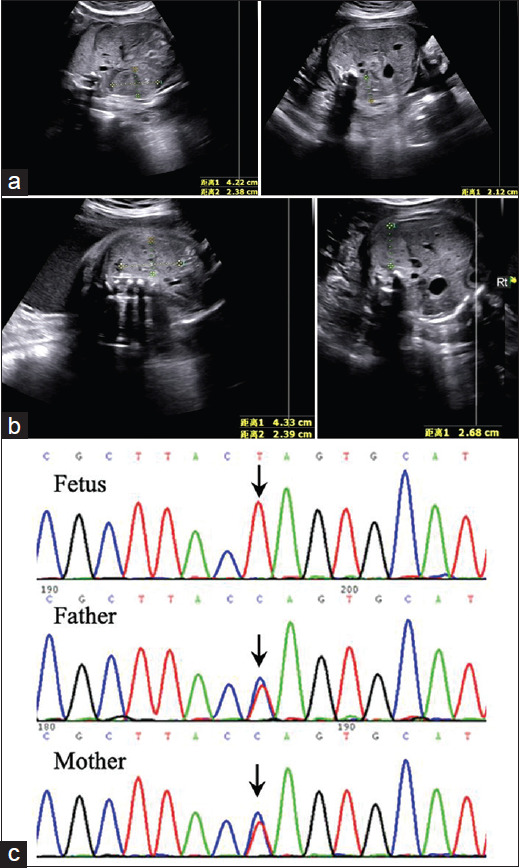

Sonographic Findings in Two Consecutive Pregnancies Affected with Fetuses of Congenital Nephrotic Syndrome of Finnish Type.